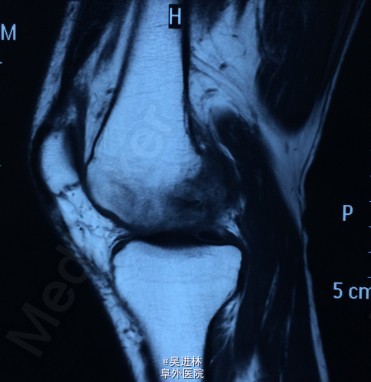

患者6个月前无明显诱因出现左膝关节内侧间隙疼痛,就诊于当地医院,诊断为骨坏死(骨髓水肿易误诊为骨坏死),行左股骨内侧髁开窗病灶清除术。一月前无明显诱因再次出现左膝关节外侧间隙疼痛,无法行走,站立及上下楼梯,无发热,无腰痛,无下肢肿胀,我院诊断为“骨髓水肿”。骨髓水肿发生于单髁是比较少见的,通常累及整块骨头,这个病人不仅在单髁发生骨髓水肿,而且奇怪的是,左侧髁水肿好了之后,外侧髁侧又出现了水肿。